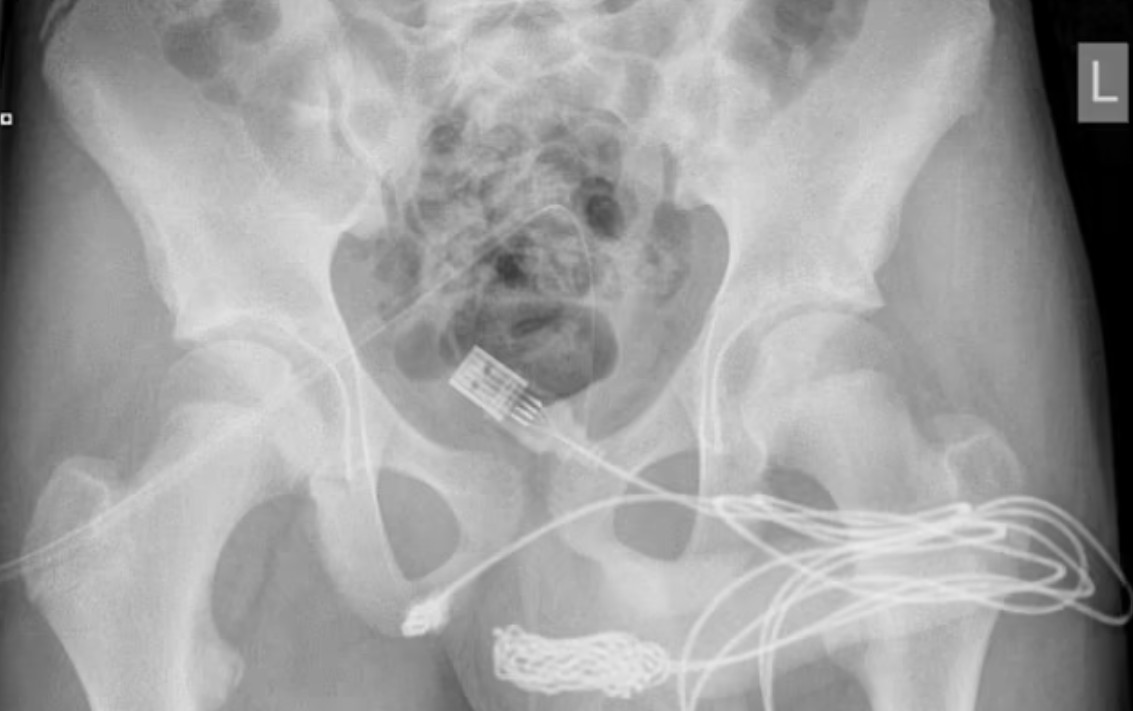

Απέναντι σε ένα… περίεργο περιστατικό βρέθηκαν οι γιατροί σε νοσοκομείο της Βρετανίας, αφού κλήθηκαν να αφαιρέσουν ένα καλώδιο USB από το πέος 15χρονου, το οποίο είχε… σφηνώσει.

Δείτε εικόνα της ακτινογραφίας του 15χρονου